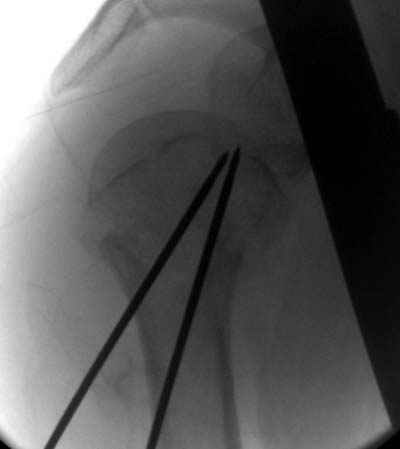

Здесь случай перелома-вывиха плеча, больному 56 лет, после "дважды" закрытой неудачной репозиции, опять же ургентно взяли в операционную, после полного общего обезболивания попытались сделать репозицию, и фиксацию провели спицами.

Больной находился в повязке, примерно напоминяющей косыночную, рекомендованы движения в локтевом суставе и маятниковые движения в плече, спицы удалены в три недели (были случаи миграции)

Клинические снимки - 3 недели после операции

Посылаю послеоперационные Рг граммы.